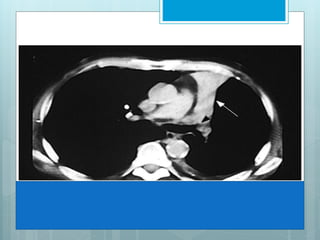

This image shows complete opacification of most of left upper lobe. When bronchi

remain aerated, they are seen as branching lucencies called air-bronchograms. This

image represents infectious pneumonia, limited by major fissure, resulting in a sharp

border.

This image showscomplete opacification of most of left upper lobe. When bronchi remain aerated, they are seen as branching lucencies called air-bronchograms. This image represents infectious pneumonia, limited by major fissure, resulting in a sharp border.